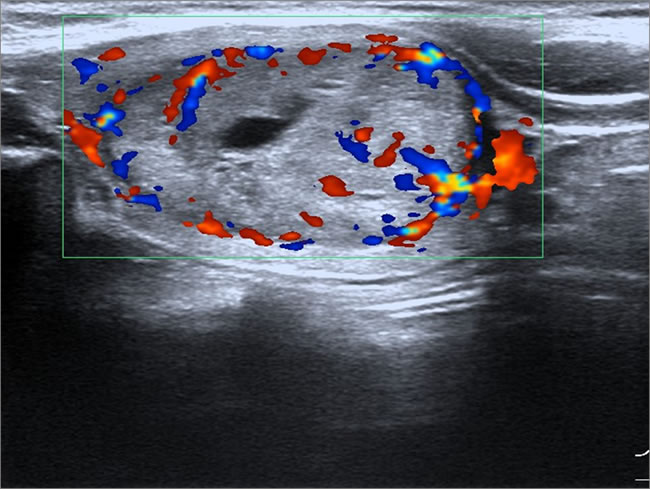

Figure 4: Female patient, 35 years old, sporadic MTC. Lesion had aspect ratio < 1, enhanced blood flow.

Specific ultrasound characteristics of 44 MTCs and 119 PTCs are shown in Table 3. Like PTC, MTC showed ultrasonographic features of malignant nodules, including marked hypoechogenicity (37/44, 84.1%), ill-defined margin (28/44, 63.6%), microcalcifications (24/44, 54.5%), and abnormal cervical lymph node (16/35, 45.7%). However, compared with PTC, MTC had significantly larger lesion size (2.10 ± 1.70 cm vs. 0.80 ± 0.70 cm, P < 0.001). Most of the lesions in MTC were oval shaped (Figure 1). The MTC group only had three lesions (3/44, 6.8%) with aspect ratio > 1, which was significantly less than the PTC group (68/119, 57.1%, P < 0.001) (Figure 2). The MTC group had seven lesions (7/44, 15.9%) with a mixed echogenicity (Figures 1 and 3); this was significantly higher than the PTC group (3/119, 2.5%, P = 0.003). The MTC group had 40 lesions with enhanced blood flow signals (40/44, 90.9%) (Figure 4), which was significantly higher than the PTC group (47/119, 39.5%, P < 0.001). Both MTC and PTC groups showed abnormal cervical lymph nodes; the MTC group had 16 cases (16/35, 45.7%) and the PTC group had 32 cases (32/96, 33.3%). The difference between the two groups was not statistically significant (P = 0.21).

In our study, about half the lesions in MTC and PTC groups had visible microcalcifications, and there was no significant difference between these two groups (P = 0.488). Most of the lesions in the MTC group had enhanced blood flow signals (40/44, 90.9%), which was significantly higher than for the PTC group (47/119, 39.5%, P < 0.001). Saller et al. [19] suggest that grayscale ultrasound is an important means of thyroid nodule examination, and state that detection of intranodular blood flow by color Doppler sonography provides no additional information for the diagnosis of MTC or other malignant nodules. The intensity of ultrasonic blood flow signals is related to a variety of factors, such as tumor size and tumor-specific pathological type. Foschini et al. [20] found that the vascular composition of MTC is similar to that of the differentiated mast cell tumors, in which the peripheral blood vessels invade and differentiate into smaller vessels.